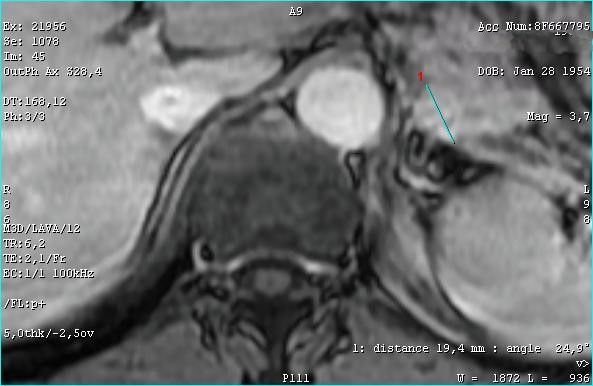

Опухоль хвоста панкреас

Пожилой мужчина. Жалоб не предъявляет.